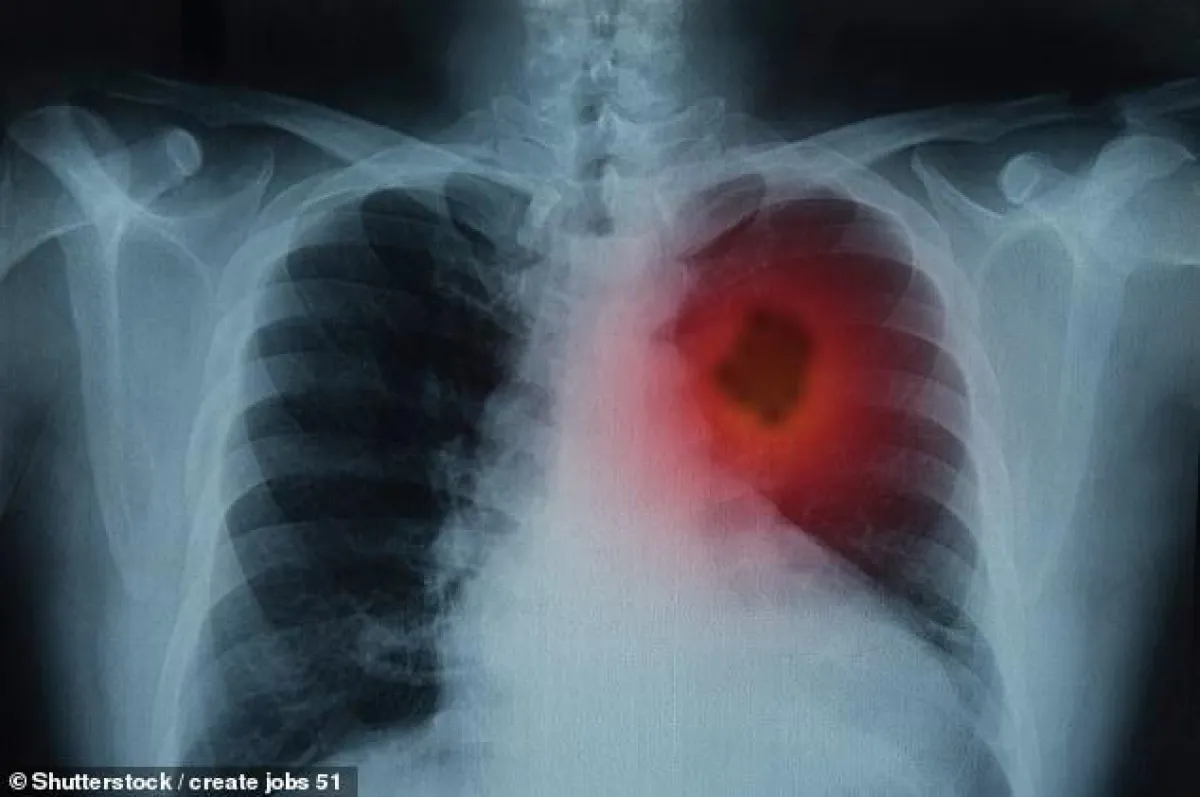

بعد أن أثبتت دراسات عديدة، أكد نتائجها أهم وأشهر أطباء مرض السرطان بأن المدخنين الأكثر عرضة للإصابة بسرطان الرئة، أبرزت إحصائيات طبية إصابة ثلث البشر في بعض الدول من فئة غير المدخنين بمرض سرطان الرئة. وفي القرن الحادي والعشرين تحديداً ارتفع عدد إصابات غير المدخنين بمرض سرطان الرئة.

يصاب الآلاف بسرطان الرئة القاتل على الرغم من أنهم لم يدخنوا سيجارة على الإطلاق، الأمر الذي يثير تساؤلات حول كيفية حدوث ذلك. وتضاعفت أعداد المصابين بـ«سرطان الرئة» من غير المدخنين في السنوات الأخيرة، بحسب دراسات طبية حديثة.

وفي الواقع، فإن التدخين يعتبر عاملاً رئيسيًا في الإصابة بسرطان الرئة، نظرًا إلى وجود نحو 60 عاملاً كيماويًا مسرطنًا في السيجارة، وأنه مسؤول عن 85 في المئة من حالات الإصابة بهذا النوع من السرطان، فإن الباحثين يعتقدون أن الإصابة بالمرض بين فئة «غير المدخنين» تشهد زيادة في السنوات الأخيرة.

وبحسب دراسة قام بها الباحث والمستشار في جراحة الصدر في مستشفى برومبتون الملكي «إريك ليم» فإن عدد حالات الإصابة بمرض سرطان الرئة بين غير المدخنين تضاعف في السنوات الأخيرة.

ووفق الدراسة التي نشرت في دورية السرطان الأوروبية، فإن عدد من أجروا عمليات جراحية لإصابتهم بسرطان الرئة من غير المدخنين بلغت نحو ثلث إجمالي هذا النوع من العمليات الجراحية.

ويوضح ليم أن هناك صعوبة في تشخيص غير المدخنين بمرض سرطان الرئة، وهذا يعني أنه لا يتم الكشف عن الإصابة بالمرض إلا في مراحله المتأخرة، وعندما يصبح العلاج أكثر صعوبة.